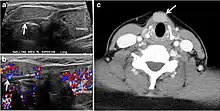

Fig. 7. A 51-year-old female patient post total thyroidectomy for PTC with elevated thyroglobulin measurement. an Axial non-enhanced CT scan of the neck at the level of the thyroid bed demonstrates a well-defined, rounded, homogenously dense soft tissue situated between the trachea and left internal jugular vein (white arrow). b Transverse ultrasound image of the neck demonstrates a well-defined, homogeneous, hypoechoic soft tissue nodule measuring 6 mm (white arrow) with no detected micro-calcifications. Biopsy showed a predominantly residual normal thyroid tissue with micro-foci of PTC.[1]